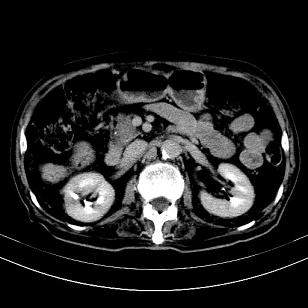

标题: CT19407:肝内还是肝外原发性肿瘤??

男,63岁,高血压病史40余年,

来源-右侧肾上腺。

考虑右侧肾上腺巨大占位;恶性?

肝内多发低密度找;转移瘤?

另:右肾结识,多发小囊肿。

考虑右肝后叶肝癌(部分外生)伴肝内多发性转移;右侧肾上腺区恶性肿瘤并肝转移待排。

考虑右侧肾上腺肿瘤并肝内多发转移。右侧肾上腺呈“八”字形,包括内侧枝及外侧枝,内侧枝受压,考虑外侧枝原发肿瘤。”

考虑肝右后叶肝癌(部分外生)伴肝内多发性转移;不排除右侧肾上腺区恶性嗜铬细胞瘤并肝转移。